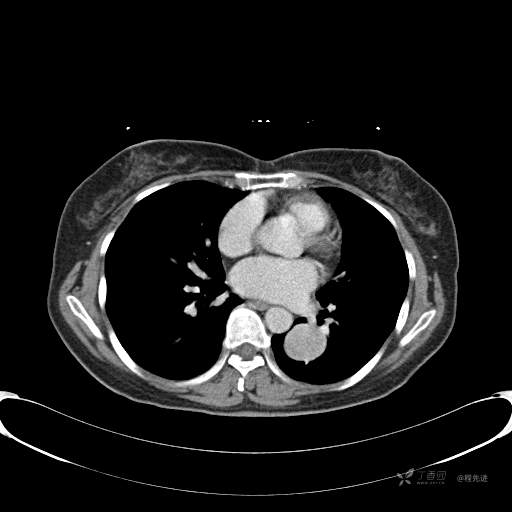

患者性别:女

患者年龄:57岁

简要病史:体检发现

CT增强

平扫CT值约40HU(未上传图像),增强后动脉期CT值约70HU,静脉期CT值约97HU。